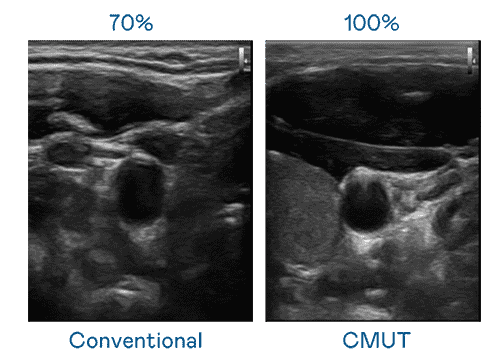

CMUT 技术是一种用电容式微机电元件来产生超音波讯号的技术。。与传统 PZT 压电式技术相比,,,CMUT 频宽增加 30%,,,更宽频的超音波讯号让影像解析度大幅提升,,是实现高影像品质医疗超音波扫描、、、、促进精准医疗发展的关键技术。。。

超音波影像的解析度高低,,,首先取决于探头能发出的讯号频宽。。。传奇国际 CMUT 可提供高清晰的超音波讯号,,,,提供高频宽、、高灵敏度、、影像纹理细节更高的超音波影像,,协助医护人员缩短影像判读时间及利用精准的医疗影像进行诊断。。